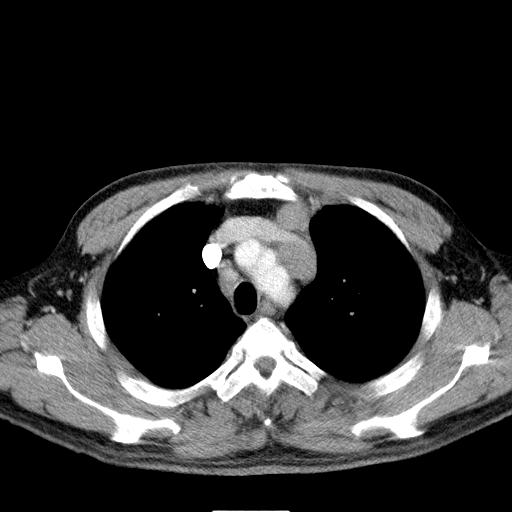

经典?纵膈多发肿大淋巴结。腹膜后未见异常。

淋巴瘤?胸腺瘤?

1)考虑淋巴瘤。2)双侧少量胸腔积液。